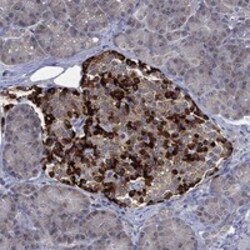

Supportive validation

- Submitted by

- Invitrogen Antibodies (provider)

- Main image

- Experimental details

- Immunohistochemical analysis of SELENOO in human pancreas using SELENOO Polyclonal Antibody (Product # PA5-140354) shows strong cytoplasmic positivity in islets of Langerhans.